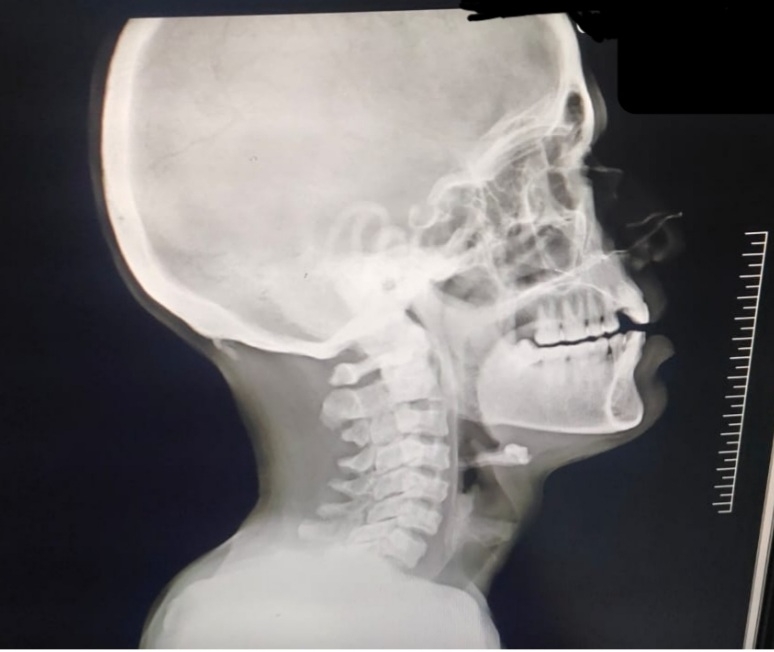

X ray C spine showing early spondylitis changes